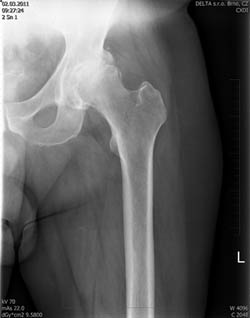

Na rentgenovém snímku se artróza projevuje postupným zužováním kloubní štěrbiny, nárůstem okrajových osteofytů, subchondrální sklerózou, někdy až tvorbou subchondrálních cyst s možností vzniku nekrózy kosti.

Artrózu dělíme dle RTG nálezu na čtyři stádia dle Kellgrena a Lawrence (1957):

- I. stadium: zúžení kloubní štěrbiny mediálně, počátek tvorby osteofytů

- II. stadium: určité snížení kloubní štěrbiny inferomediálně, zřetelné osteofyty

- III. stadium: kloubní štěrbina výrazně zúžena, osteofyty, sklerotické změny detritové cysty, deformace tvaru hlavice i acetabula

- IV. stadium:vymizení kloubní štěrbiny se sklerózou a cystami, pokročilá deformace